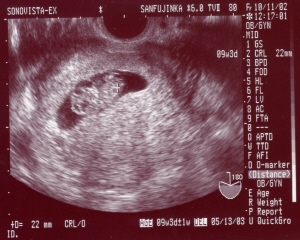

10/11A‹ßŠ‚ÌŽY•wl‰È‚És‚Á‚Ä‚«‚Ü‚µ‚½B

¡A‚XTC‚Q.‚Qmm‚¾‚»‚¤‚Å‚·B

oŽY—\’è“ú‚Í —ˆ”N‚Ì‚T^‚P‚R(^^;